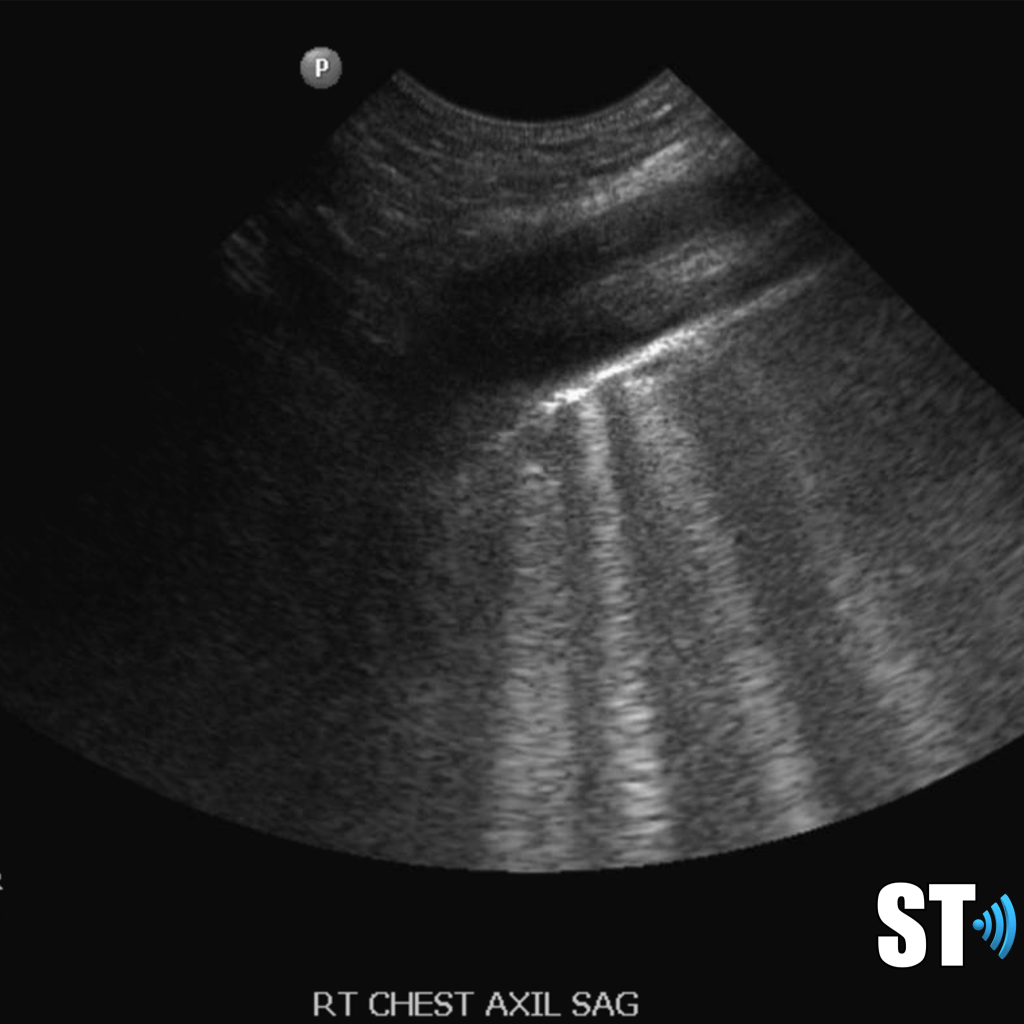

Moderate to large pleural effusion and pleural fluid anterior to lung

Large volume pleural effusion

Pleural effusion is a build up of fluid between the layers of the pleura. Scanning subcostally will show fluid above the diaphragm. Scanning intercostally will show fluid anterior the lung. Common causes for pleural effusion is infection, inflammation and malignancy.

The fluid can be anechoic or echogenic in cases of increased exudates, empyema, hemothorax and chylothorax (lymph collection). There may also be septations.